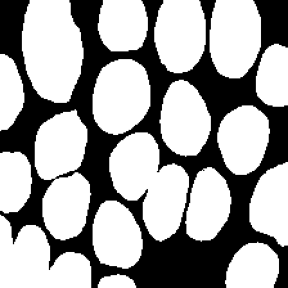

Microscopic image segmentation is a challenging task, wherein the objective is to assign semantic labels to each pixel in a given microscopic image. While convolutional neural networks (CNNs) form the foundation of many existing frameworks, they often struggle to explicitly capture long-range dependencies. Although transformers were initially devised to address this issue using self-attention, it has been proven that both local and global features are crucial for addressing diverse challenges in microscopic images, including variations in shape, size, appearance, and target region density. In this paper, we introduce SA2-Net, an attention-guided method that leverages multi-scale feature learning to effectively handle diverse structures within microscopic images. Specifically, we propose scale-aware attention (SA2) module designed to capture inherent variations in scales and shapes of microscopic regions, such as cells, for accurate segmentation. This module incorporates local attention at each level of multi-stage features, as well as global attention across multiple resolutions. Furthermore, we address the issue of blurred region boundaries (e.g., cell boundaries) by introducing a novel upsampling strategy called the Adaptive Up-Attention (AuA) module. This module enhances the discriminative ability for improved localization of microscopic regions using an explicit attention mechanism. Extensive experiments on five challenging datasets demonstrate the benefits of our SA2-Net model. Our source code is publicly available at \url{https://github.com/mustansarfiaz/SA2-Net}.